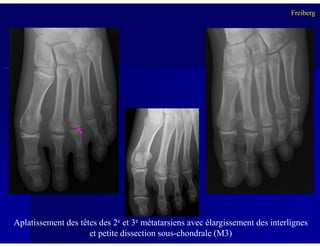

Aplatissement des têtes des 2e et 3e métatarsiens avec élargissement des interlignes

et petite dissection sous-chondrale (M3)